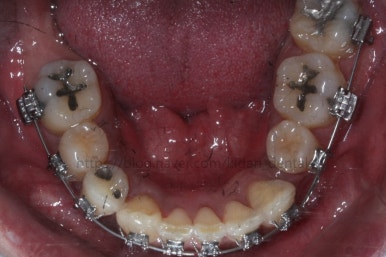

부산치아교정 키다리아저씨치과에서 치료를 시작한지 2년 경과시 모습입니다.

이 뽑은 틈도 어느 정도 다 닫혀가고, 애를 먹이던 왼쪽 아래 작은 어금니도 많이 좋아졌어요.

여전히 약간은 불만족스러워 갖가지 방법을 동원해서 바로 잡아주고 있어요.

2년 2개월째 이빈다.

이제 거의 다 되어간다고 보면 되겠고, 좀 더 디테일한 마무리를 하고 끝내면 되겠습니다.

드디어 치료 종료시의 모습입니다. 2년 4개월 걸렸네요.

앞니 안쪽에는 유지철사를 붙여주었고요. 임플란트가 필요한 부위랑 맞닿은 부분은 치열이 움직이지 않도록 철사로 잡아주었어요.(오른쪽 어금니 부위)

삐뚤었던 치아들이 가지런해졌습니다.

왼쪽 송곳니를 발치했지만 별로 표시가 안나게 마무리를 했습니다.

많이 썩은 치아들은 다 뽑았고, 틈새도 다 다물어졌습니다.

원래 패여 있던 부위는 완벽하게 만들기는 힘들지만 앞으로 관리를 잘해주시면 이 모습 그대로 오래 사용하실 수 있으실거에요.